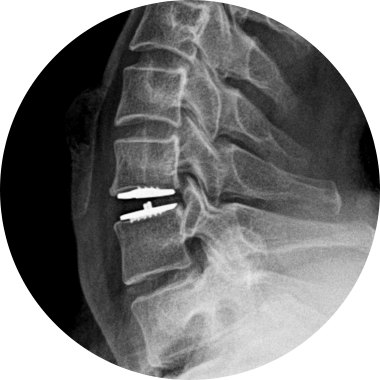

손상된 경추 디스크를 제거한 후, 척추체 사이에 인공디스크를 삽입하는 수술적 치료입니다.

손상된 경추 디스크를 모두 제거하고 빈 공간으로 인공디스크를 삽입하여 본래의 디스크처럼 정상적인 기능을 하도록 합니다.

경추 인공디스크 치환술 후 자유로운 목 움직임